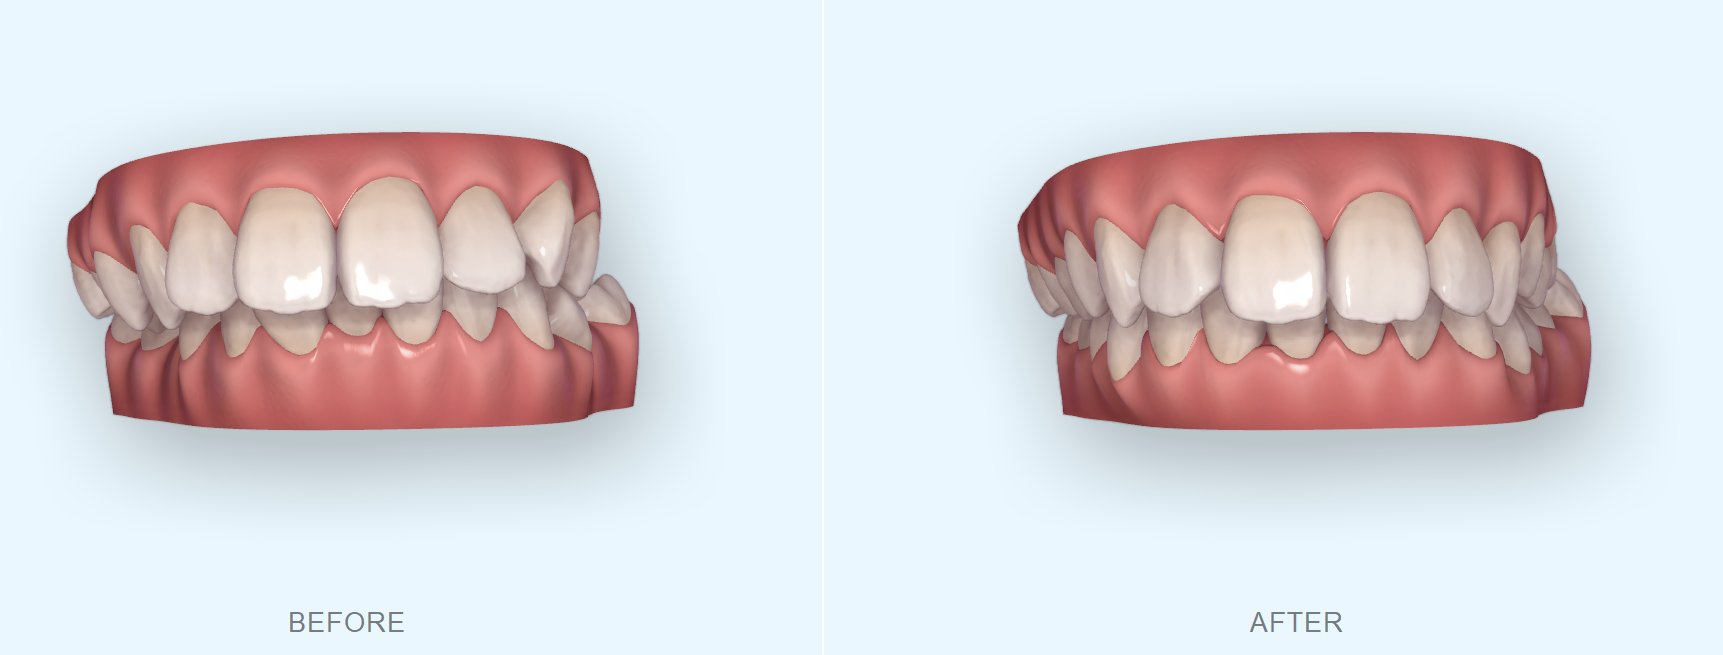

初診時の画像

結論から述べると、部分矯正だけで前歯のガタガタと出っ歯を両方とも治療するのはかなり困難です。前歯のガタガタの原因は歯の大きさと顎の大きさのバランスが悪いために前歯が綺麗に並ばないのです。顎を満員電車に例えると満員電車にさらに人が入ろうとしてぎゅうぎゅうになってしまっているのです。このような場合には①抜歯を行う、②歯を削って小さくする+歯並びを少し拡大するといった治療を行うことでガタガタを解消します。しかし、今回のように出っ歯もガタガタも気になる場合には、基本的には抜歯を行わなければ、歯を内に入れてガタガタを解消することができないのです。抜歯を行う場合は基本的には部分矯正では治療を行えませんので、今回K.Kさんの場合は全体の矯正治療が必要になります。

今回の症例では、前歯部の叢生および上顎前突を主訴に来院された患者様のご相談内容でした。

このように大きなガタガタがなくとも前歯の突出感もなくしたい場合には部分矯正のみで行うことは困難です。